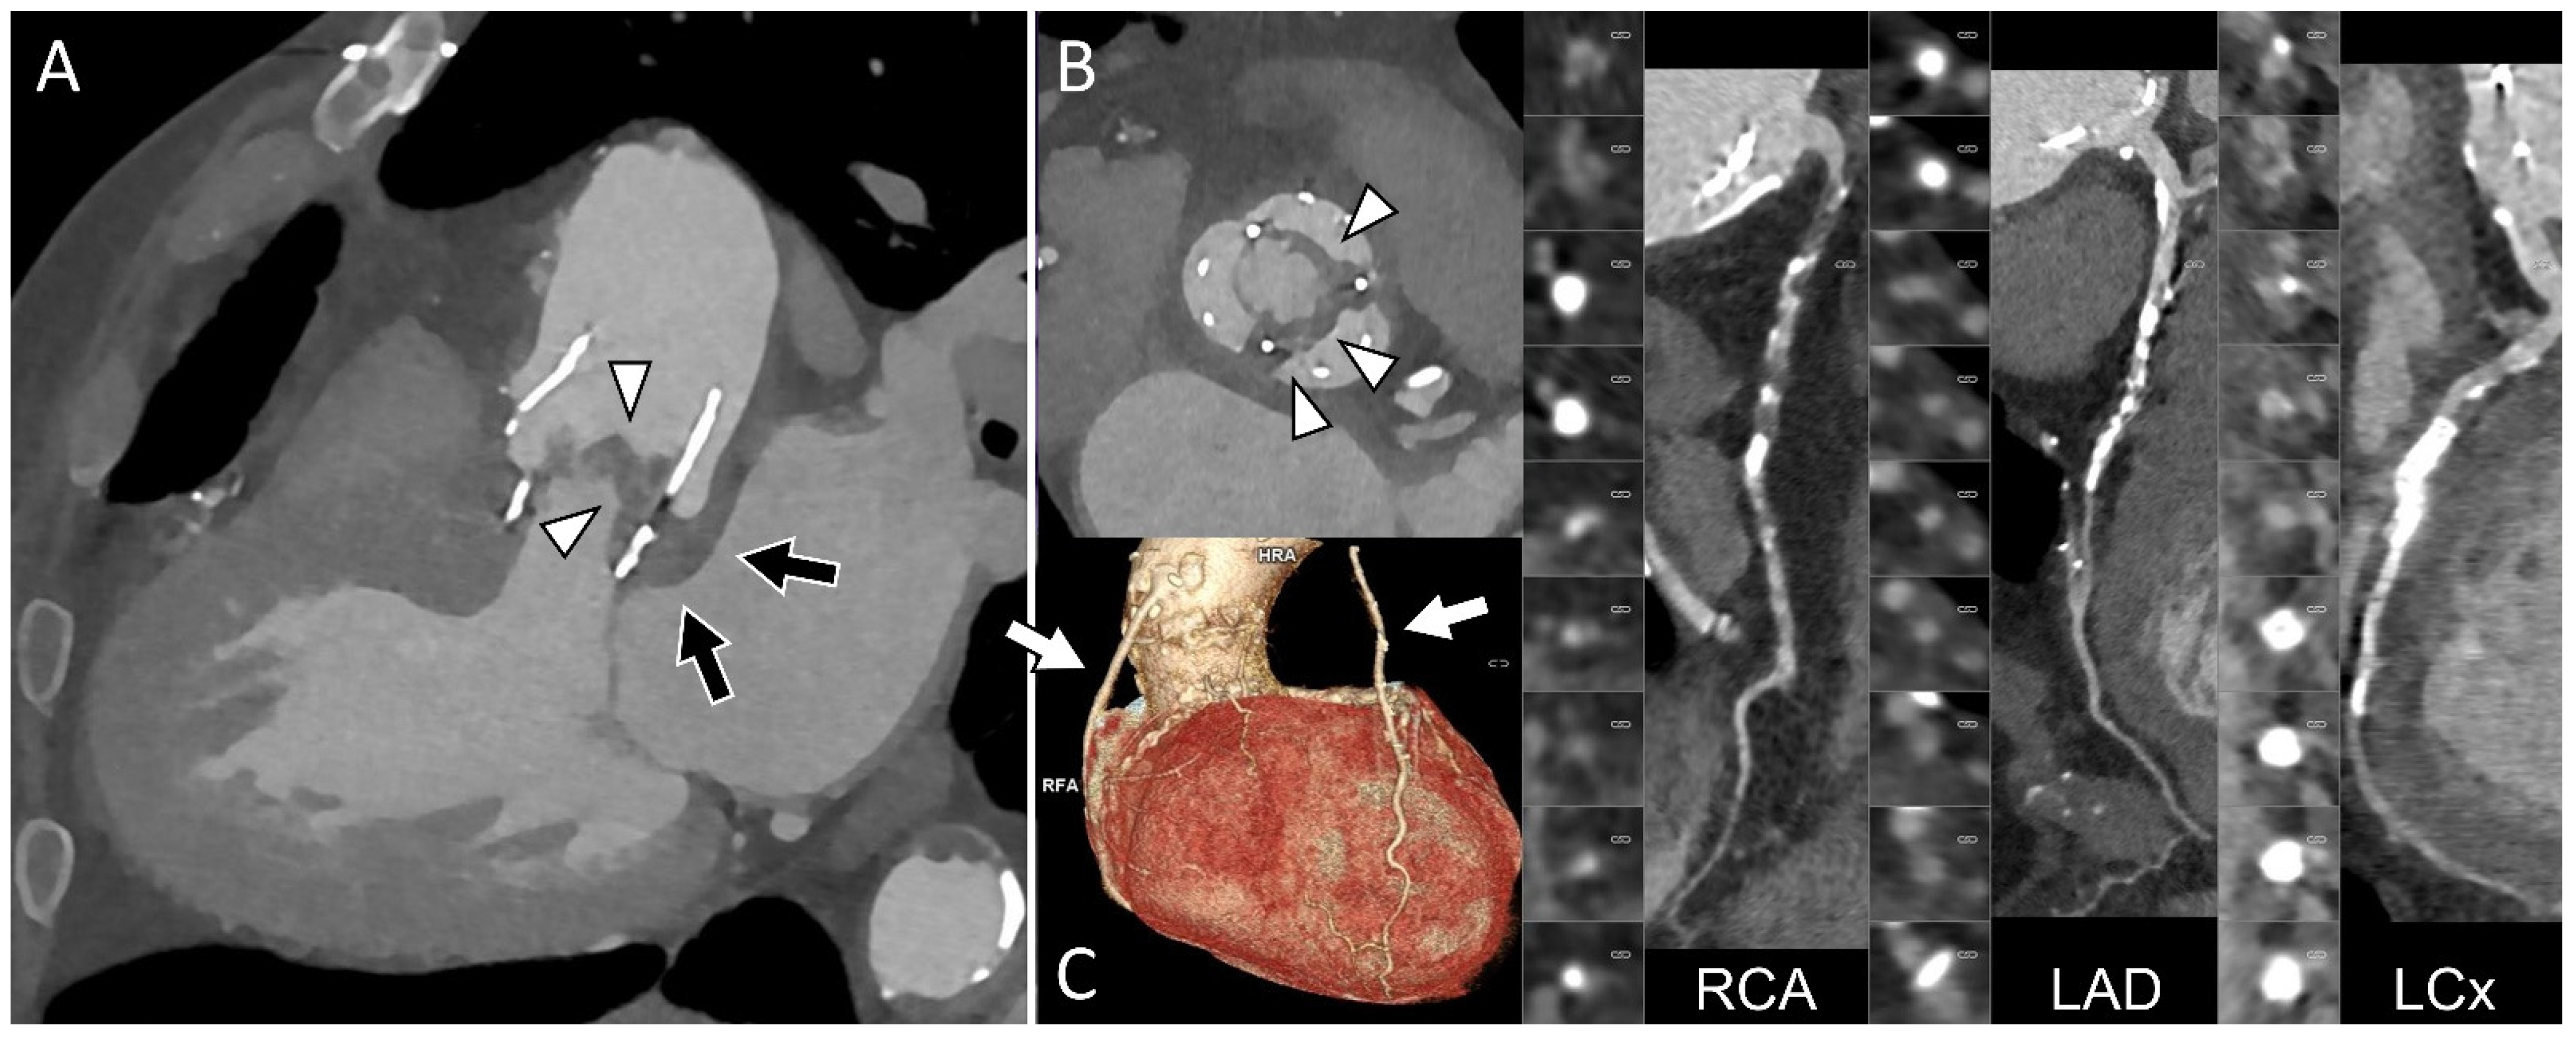

Since Perceval valve implantation is usually selected for patients at moderate to high surgical risk, particularly elderly patients [48], some individuals with Perceval valve endocarditis may be considered poor candidates for cardiac surgery and managed with long-term antibiotic therapy. In this context, PET/CT findings can support clinical decision-making and may be used to monitor the response to antimicrobial treatment [48]. Figure 2 highlights the importance of a comprehensive CT assessment, whereas Figure 3 presents a case of endocarditis with spondylodiscitis, illustrating the value of PET/CT in a patient with inconclusive echocardiographic findings.

Figure 2. Comprehensive cardiac CT assessment in prosthetic valve endocarditis involving a Perceval sutureless valve. Echocardiography was diagnostic for valvular vegetations, but the presence and extent of perivalvular involvement remained uncertain. Cardiac CT was therefore performed to evaluate periprosthetic complications and to assess coronary anatomy prior to surgery. Three-chamber (A) and aortic plane (B) views confirm leaflet vegetations (arrowheads) associated with extensive periprosthetic soft-tissue thickening extending to the mitral–aortic fibrosa (black arrows), consistent with a perivalvular abscess ((A), black arrows). CT coronary angiography demonstrated severe and diffuse coronary artery disease but patency of two coronary bypass grafts ((C), arrows), neither of which was in close proximity to the predicted re-sternotomy plane.